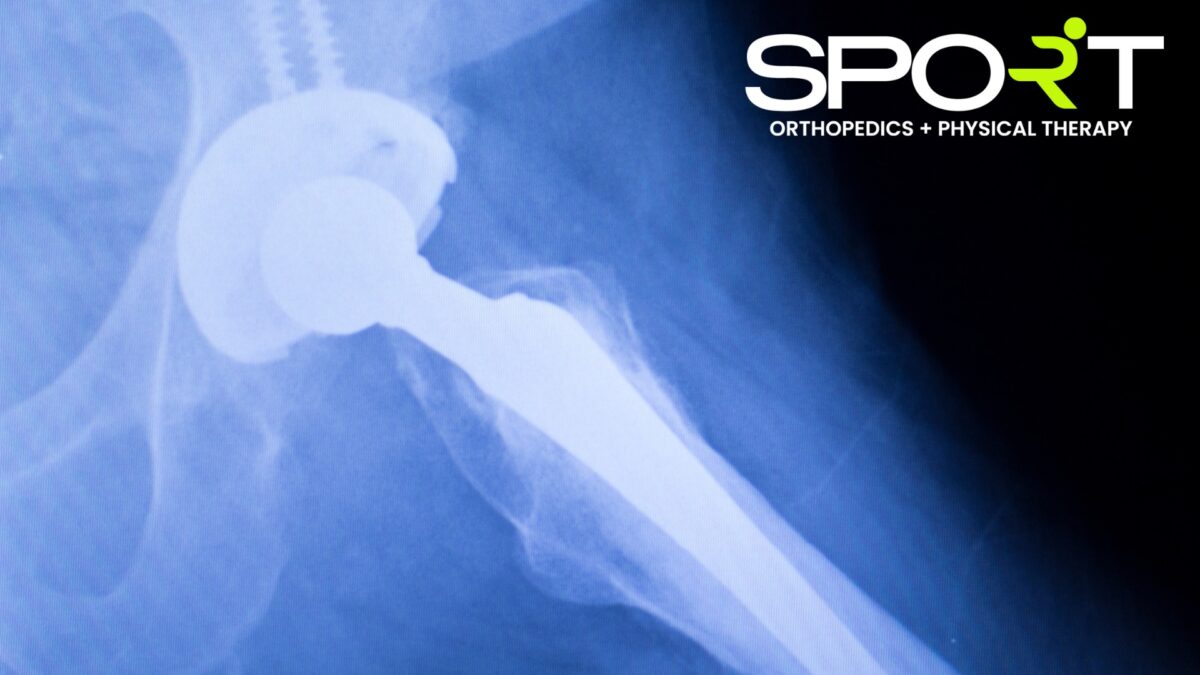

If you suffer from osteoarthritis, a degenerative joint disease, your doctor might recommend that you have hip replacement surgery. While osteoarthritis is the most common reason for patients to undergo hip replacement surgery, those that have rheumatoid arthritis, an autoimmune disorder that affects the joints, and osteonecrosis, when part of the bone dies due to decreased blood flow, can also benefit from hip replacement surgery. If you’ve broken or fractured your hip from an injury or degenerative bone disease, your doctor may recommend hip replacement surgery. If you have trouble sleeping due to hip pain or difficulty performing simple tasks, you might want to talk to your doctor today. At SPORT, our orthopedic doctors will get you back to living a pain-free lifestyle in no time.